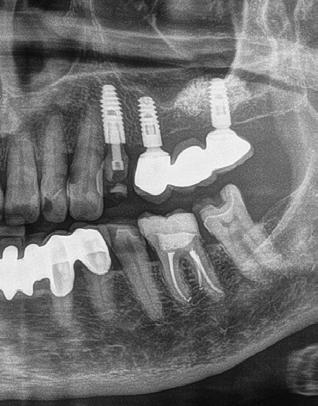

A korai harmicas éveiben járó hölgy rendelőnkbe érkezésének oka a jobb felső nagymetsző fog bizonytalan érzkenysége, elmondása alapján gyermekkorában trauma érte a felső frontrégiót. A frakturált klinikai koronákat kompozittöméssel helyreállították, egyéb kezelést akkor nem tartottak szükségesnek. Az utóbbi hónapokban tapasztalt érzékenység miatt kereste fel rendelőnket. A klinikai vizsgálat (1. és 2. kép) és a CBCT felvétel (3. kép) alapján diagnosztizált külső gyökérreszorpció megoldására a fog eltávolítását, implantátum

behelyezését, majd csavarozott rögzítésű, cirkónium-dioxid vázas, kerámialeplezésű korona készítését terveztük [1., 5., 6., 8.].

1. ábra: Megfelelő szájhigiénia – panorámaröntgen. 2. ábra: A 2.5, 2.6 és 2.7-nek megfelelő terület a röntgenfelvételen.

és jelentős mobilitással rendelkezett. A radiológiai vizsgálat után egyértelműen látszódott, hogy a fogon még nem végeztek gyökérkezelést. A 2.6-os és 2.7-es fogaknak megfelelő területen az arcüreg kiterjedése jelentős volt, vertikális csontmennyiség szignifikánsan csökkent (1. és 2. ábra).